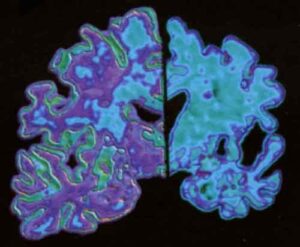

Alzheimer: attenzione ai vuoti di memoria in soggetti anziani

Vuoti di memoria improvvisi negli anziani e difficolta’ a ricordare gli eventi piu’ recenti potrebbero essere indicativi di problemi cognitivi piu’ seri di quelli naturalmente connessi all’invecchiamento che meriterebbero un ulteriore approfondimento.